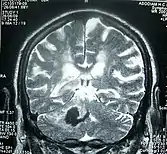

Perinatal stroke can be diagnosed with medical imaging techniques that present the brain's image. The usage of diffusion-weighted imaging with magnetic resonance imaging is effective for early diagnosis of perinatal stroke.[18] Computerized tomography (CT) is also a commonly used diagnostic technique for this disease.[37] These medical imaging techniques can show bleeding or blockage in the brain and detect damage caused by ischemic stroke or hemorrhages to the brain tissues.[38] Magnetic resonance imaging is clinically preferred to computerized tomography as it can highlight the brain’s blood flow.[37] In addition, perinatal stroke is challenging to classify on computerized tomography as the neonatal brain has higher water content.[7][38] However, in certain situations, such as the inability to transport unstable infants with severe respiratory or cardiac disorders from the intensive care unit, cranial ultrasound is used as an alternative to magnetic resonance imaging.[7] Cranial ultrasound can identify intracranial hemorrhage, intraventricular hemorrhage, large cerebral sinus venous thrombosis along with the brain’s blood flow.[7]